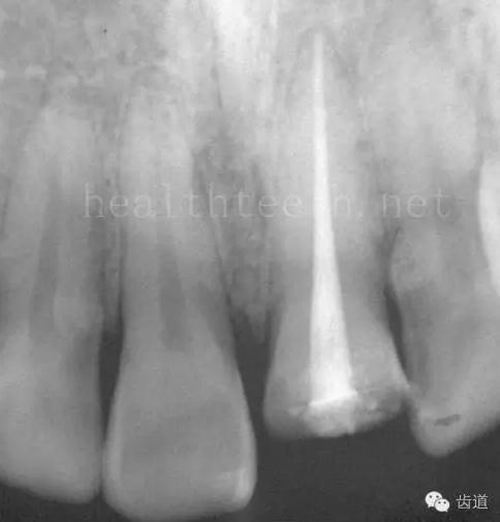

八、牙髓炎、根尖周炎

下面圖片都是慢性根尖周炎的病例,有了齲齒,進(jìn)一步發(fā)展就是牙髓炎,如果此時(shí)沒有得到及時(shí)的治療,疾病會(huì)逐漸發(fā)展破壞到根尖的骨質(zhì),將骨質(zhì)破壞后就在牙齦上出現(xiàn)一個(gè)膿瘺,此時(shí)患者不再感覺到牙齒的疼痛了,往往忽視了治療,但是這種不痛并不是疾病好轉(zhuǎn)了,而是因?yàn)榧膊〉难仔詽B出得到了引流,這個(gè)膿瘺會(huì)出現(xiàn)有時(shí)候變大了,有時(shí)候又變小了,但是如果不治療是不會(huì)自己愈合的,只有經(jīng)過完善的根管治療后才有好轉(zhuǎn)的可能,但是在疾病的治療中時(shí)間是起決定作用的,時(shí)間拖得越晚,好轉(zhuǎn)的可能性越小,經(jīng)過根管治療后如果膿瘺還是沒有消失,就需要做根尖刮治術(shù),如果仍然沒有好轉(zhuǎn),就只能做根尖切除術(shù)了,這對(duì)牙齒的穩(wěn)固是不利的。下面圖片中在膿瘺中插入了一個(gè)牙膠尖,是我們做根管充填用的材料,是非常軟的,就是在口腔牙齦瘺管的地方插進(jìn)去,通過拍牙片可以清晰地看到它到達(dá)的位置,從而確定發(fā)病的牙齒,此處是為了讓大家看得更清楚。

門牙兩個(gè)膿瘺

69.jpg

烤瓷牙修復(fù)后牙齦出現(xiàn)兩個(gè)膿瘺,插入牙膠尖,牙片顯示牙膠尖到達(dá)的位置就是根尖炎癥的位置,根尖骨質(zhì)密度降低(發(fā)黑的地方)